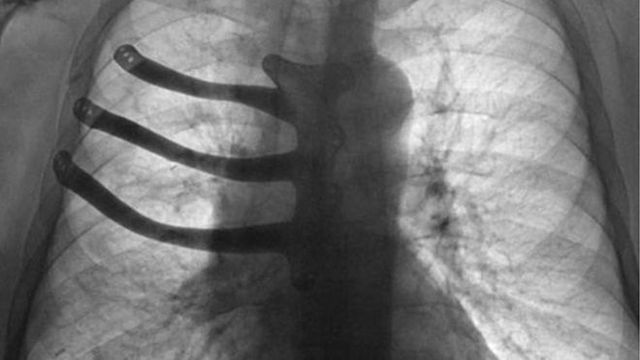

У Британії на 3D-принтері надрукували грудну клітку: фотофакт

Під час операції з видалення ракової пухлини британські лікарі реконструювали хворому груди за допомогою 3D-принтера.

"71-річному Пітеру Меггзу видалили три ребра і половину грудинной кістки, помістивши замість них протез", – йдеться в повідомленні.

За словами медиків, ракова пухлина розрослася завбільшки з тенісний м'яч і її видалення спричинило за собою великі пошкодження грудної клітки. Операція тривала вісім годин. Її провели в госпіталі Моррісон у Суонсі – другому за величиною місті Уельсу. Зазвичай в таких випадках хірурги відливають протез із спеціального медичного цементу.

Але завдяки технології 3D-друку лікарі змогли виготовити для хворого індивідуальний імплантат з титанового сплаву. "Потрібно було вирізати сильно розвинену пухлину, а разом з нею видалити частину грудної кістки і три ребра", – розповів хірург-кардіолог Айра Голдсміт. Протез із цементу довелося б робити прямо під час операції, одне це могло зайняти години півтори.